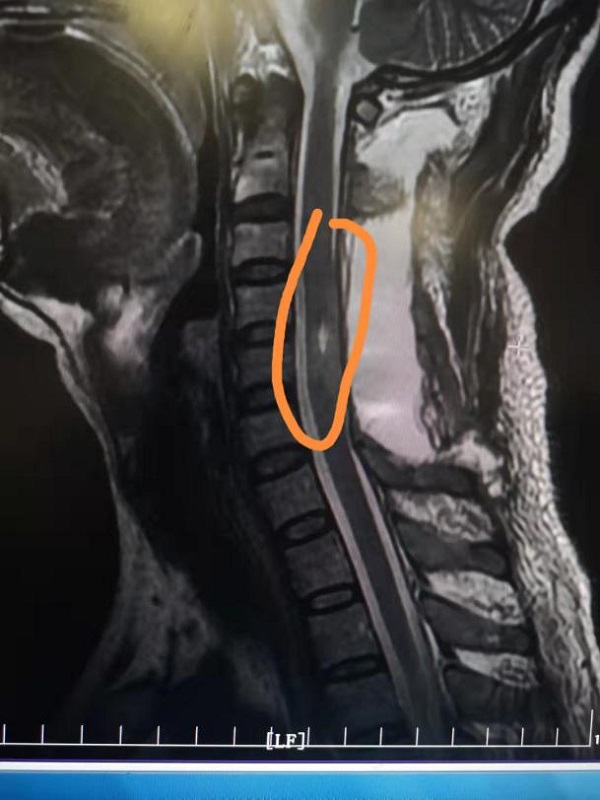

术后肿瘤复查显示肿瘤已完整切除,脊髓内残腔明显缩小。